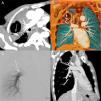

(A) Computed tomography (CT) pulmonary angiography (reconstruction with maximum intensity projection) showing a cavitated consolidation in the right upper lobe, with a highly enhancing nodule inside the cavity (arrow). Note also the relationship of the feeding vessel (arrowheads) to the pulmonary artery pseudoaneurysm (PAP; arrow). (B) Three-dimensional coronal reconstruction clearly depicts the PAP (arrow) and feeding vessel (arrowheads). (C) Pulmonary angiography performed 1 week after CT shows oligemia in the right upper lobe, with no opacification of the feeding vessel or PAP. A follow-up CT pulmonary angiography (D) demonstrated complete occlusion of the vessel and PAP, and partial resolution of the cavity.

However, a new expressive episode of hemoptysis led to a more aggressive approach, and a catheter angiogram with embolization was performed 1 week later. On angiography, the feeding vessel did not enhance (Fig. 1C), and selective catheterization was impossible. Bronchial and collateral angiography was also negative, suggesting thrombosis of the feeding vessel and PAP. The patient was discharged after computed tomography pulmonary angiography (CTPA) demonstrated complete occlusion of the vessel and PAP, and partial resolution of the cavity (Fig. 1D). The patient recovered uneventfully, with no evidence of bleeding during 1 year of follow-up.

We read with great interest the well-written scientific letter by Hamada et al.,1 who reported the case of a 79-year-old man presenting a large lung abscess associated with a pulmonary artery pseudoaneurysm (PAP). He was treated by embolization of the pulmonary artery and showed complete resolution of the PAP and abscess in follow-up examinations. We would like to report the case of a 52-year-old man who presented to the emergency department with a 30-day history of fever, malaise, and weight loss. He also reported episodes of hemoptysis. A chest X-ray showed consolidation in the right upper lobe associated with cavitation and an air-fluid level. Contrast-enhanced chest computed tomography revealed extensive necrotic consolidation and a contrast-enhanced nodule inside the consolidation, related to a peripheral pulmonary artery (Fig. 1A and B), suggesting the diagnosis of PAP. The patient's sputum was negative for acid-fast bacilli. He was referred for fiberoptic bronchoscopy with bronchoalveolar lavage. Cultures were negative for tuberculosis, but positive for Klebsiella pneumoniae. Treatment with intravenous antibiotics (ceftriaxone) was implemented, and the patient responded to therapy.